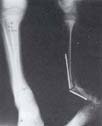

Fig 2a. Seudoartrosis congénita de tibia tipo IV de Boyd, en niño de 10 años de edad con deformidad angular de antecur-vatum 50o y varo de 40o. Acortamiento de 4 cms. c. Control radiográfico posoperatorio inicial, se observa la resección en bloque del sitio de seudoartrosis con compresión término-ter-minal y corticotomía proximal para alargamiento por distracción. |

Fig. 2b.Tomografía axial computarizada, en la que se observa la obliteración completa del canal medular y la discrepancia de longitud. |

| Fig. 2d. Control a los 45 días, finalización del alargamiento. |

Fig. 2e. 8 meses de posoperado se observa consolidación a nivel de sitio de seudoartrosis y alargamiento. |

Fig. 2f.1 año de retirado el fijador, se observa permeabilidad del canal medular y alineación de la deformidad angular en los dos planos. |